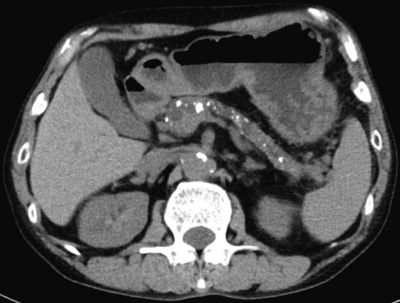

血液生化学所見:総ビリルビン 1.0 mg/dL、AST 84 U/L、ALT 53 U/L、ALP 258 U/L(基準 115〜359)、γ-GTP 110 U/L (基準8〜50)、アミラーゼ 215 U/L (基準 37〜160)、空腹時血糖 278 mg/dL、HbA1c 9.6 %(基準 4.6〜6.2)、CA19-9 32 U/mL (基準 37 以下)。腹部CTとMRCPとを示す。